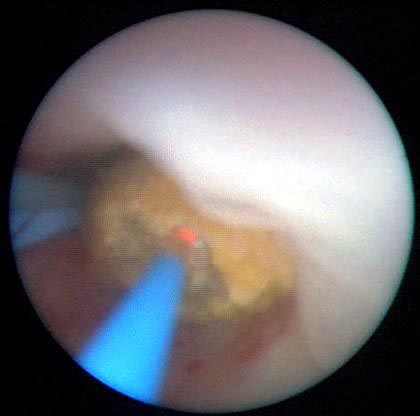

Clique nas imagens para ampliar.

• Seu momento magnético muito elevado é apropriado para a produção de lasers: Ho-YIG (cristal de ítrio e ferro) e Ho-YLF (fluoreto de ítrio e lantânio) usados em medicina e odontologia.